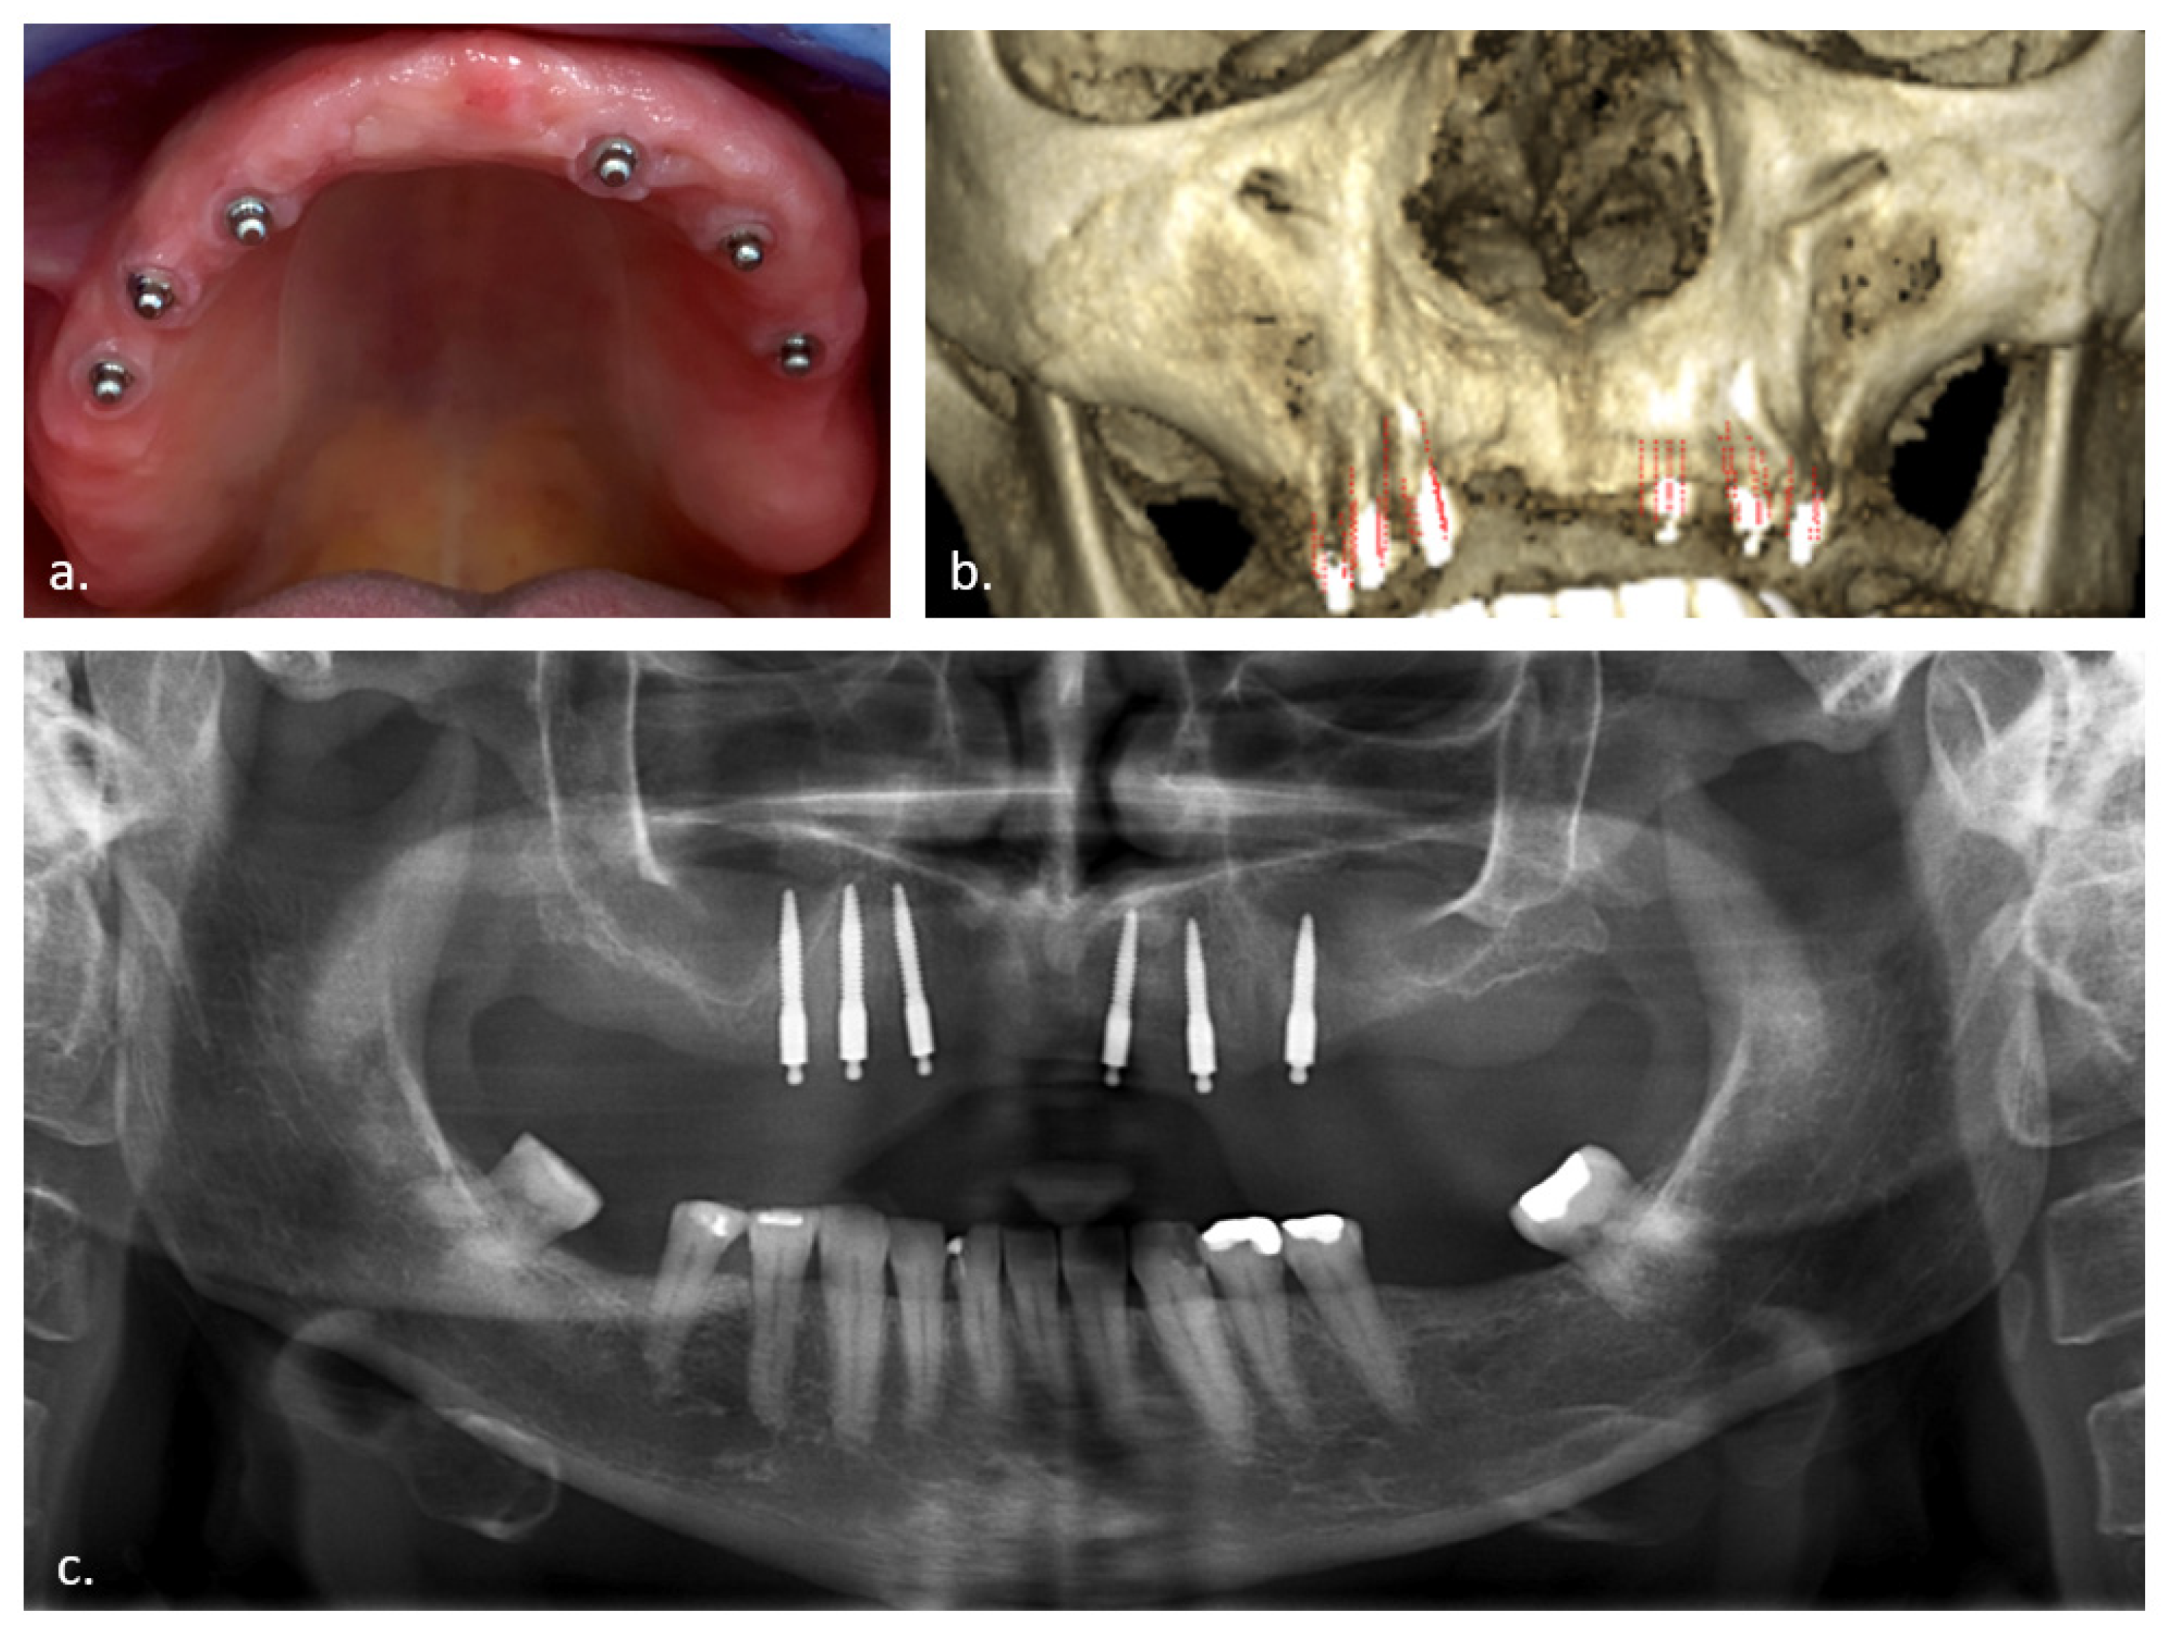

2.1. Treatment Protocol

- Van Doorne, L.; De Kock, L.; De Moor, A.; Shtino, R.; Bronkhorst, E.; Meijer, G.; De Bruyn, H. Flaplessly placed 2.4-mm mini-implants for maxillary overdentures: A prospective multicentre clinical cohort study. Int. J. Oral Maxillofac. Surg. 2019, 49, 384–391. [Google Scholar] [CrossRef]

- Van Doorne, L.; Gholami, P.; D’Haese, J.; Hommez, G.; Meijer, G.; De Bruyn, H. Three-Dimensional Radiographic Outcome of Free-Handed Flaplessly Placed Mini Dental Implants in Edentulous Maxillae after 2-Years Function. J. Clin. Med. 2020, 9, 2120. [Google Scholar] [CrossRef] [PubMed]